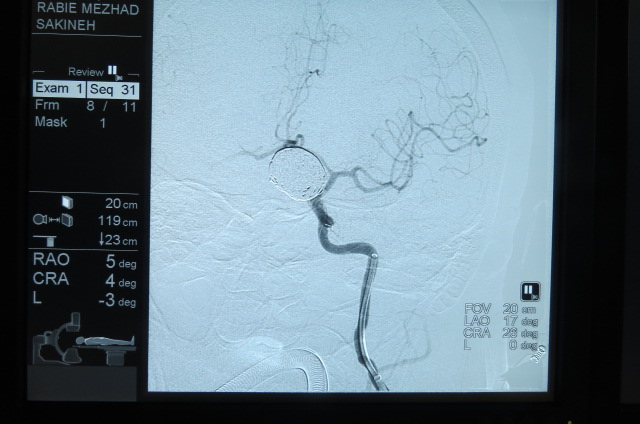

بیمار خانم 63 ساله می باشد به علت سرگیجه به بیمارستان مراجعه کرده است ، در MRI ضایعه بزرگ به اندازه 25MM گرد شبیه تومور مشاهده شده که در آنژیوگرافی مغزی ضایعه آنوریسم مغزی تشخیص داده شد،بیمار توسط تیم جراحی به سرپرستی دکتر کهنسال تحت جراحی بسته ( اینترونشن ) مغزی قرارگرفت و آنوریسم مغزی کاملا بسته شد و بیمار به بخش منتقل شد .

بر اساس گزارش به عمل آمده حال عمومی بیمار خوب می باشد . این عمل در شمال کشور و گلستان برای اولین بار انجام شد.